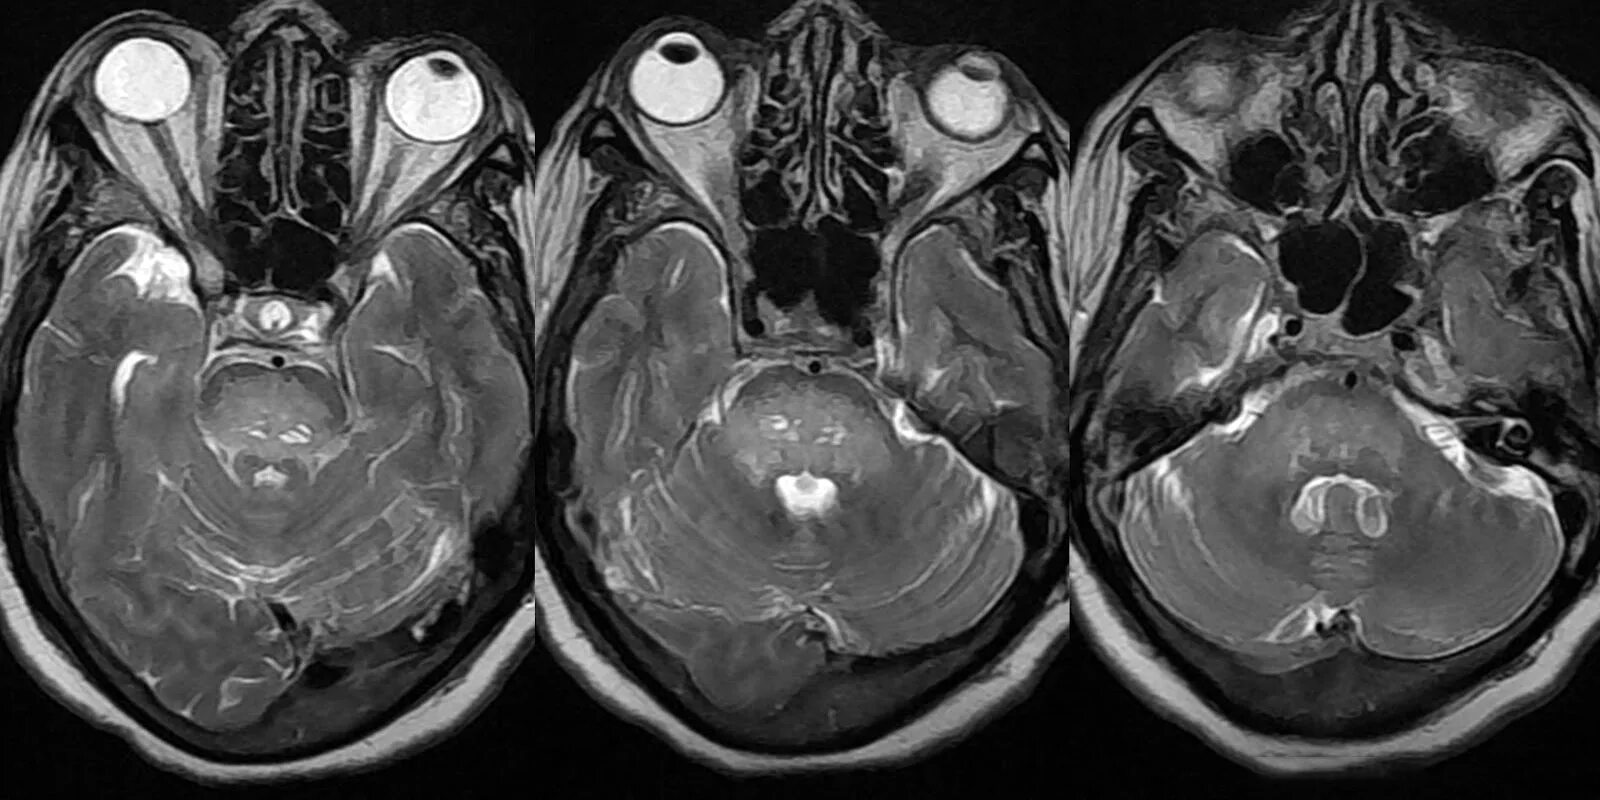

Мрт орбит и зрительных нервов